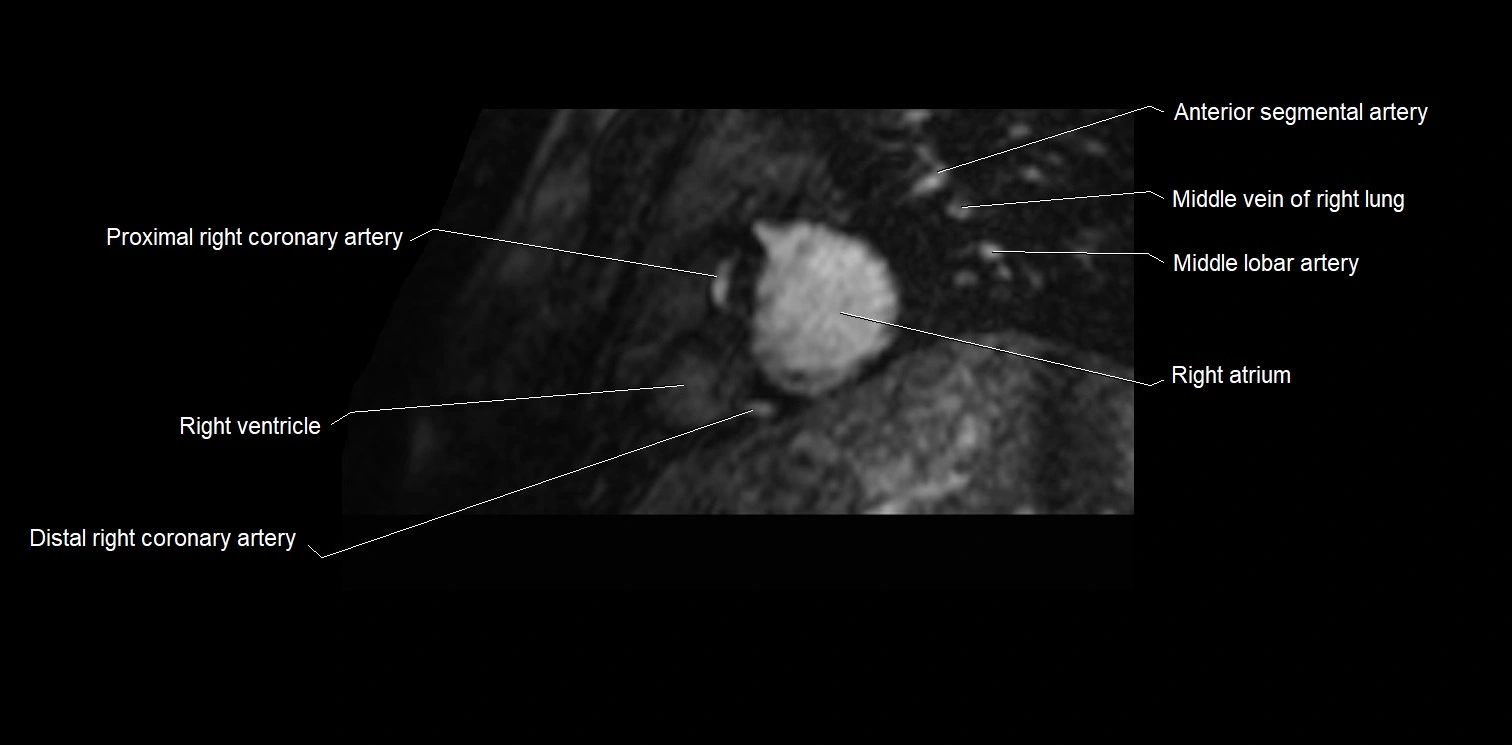

MRI image